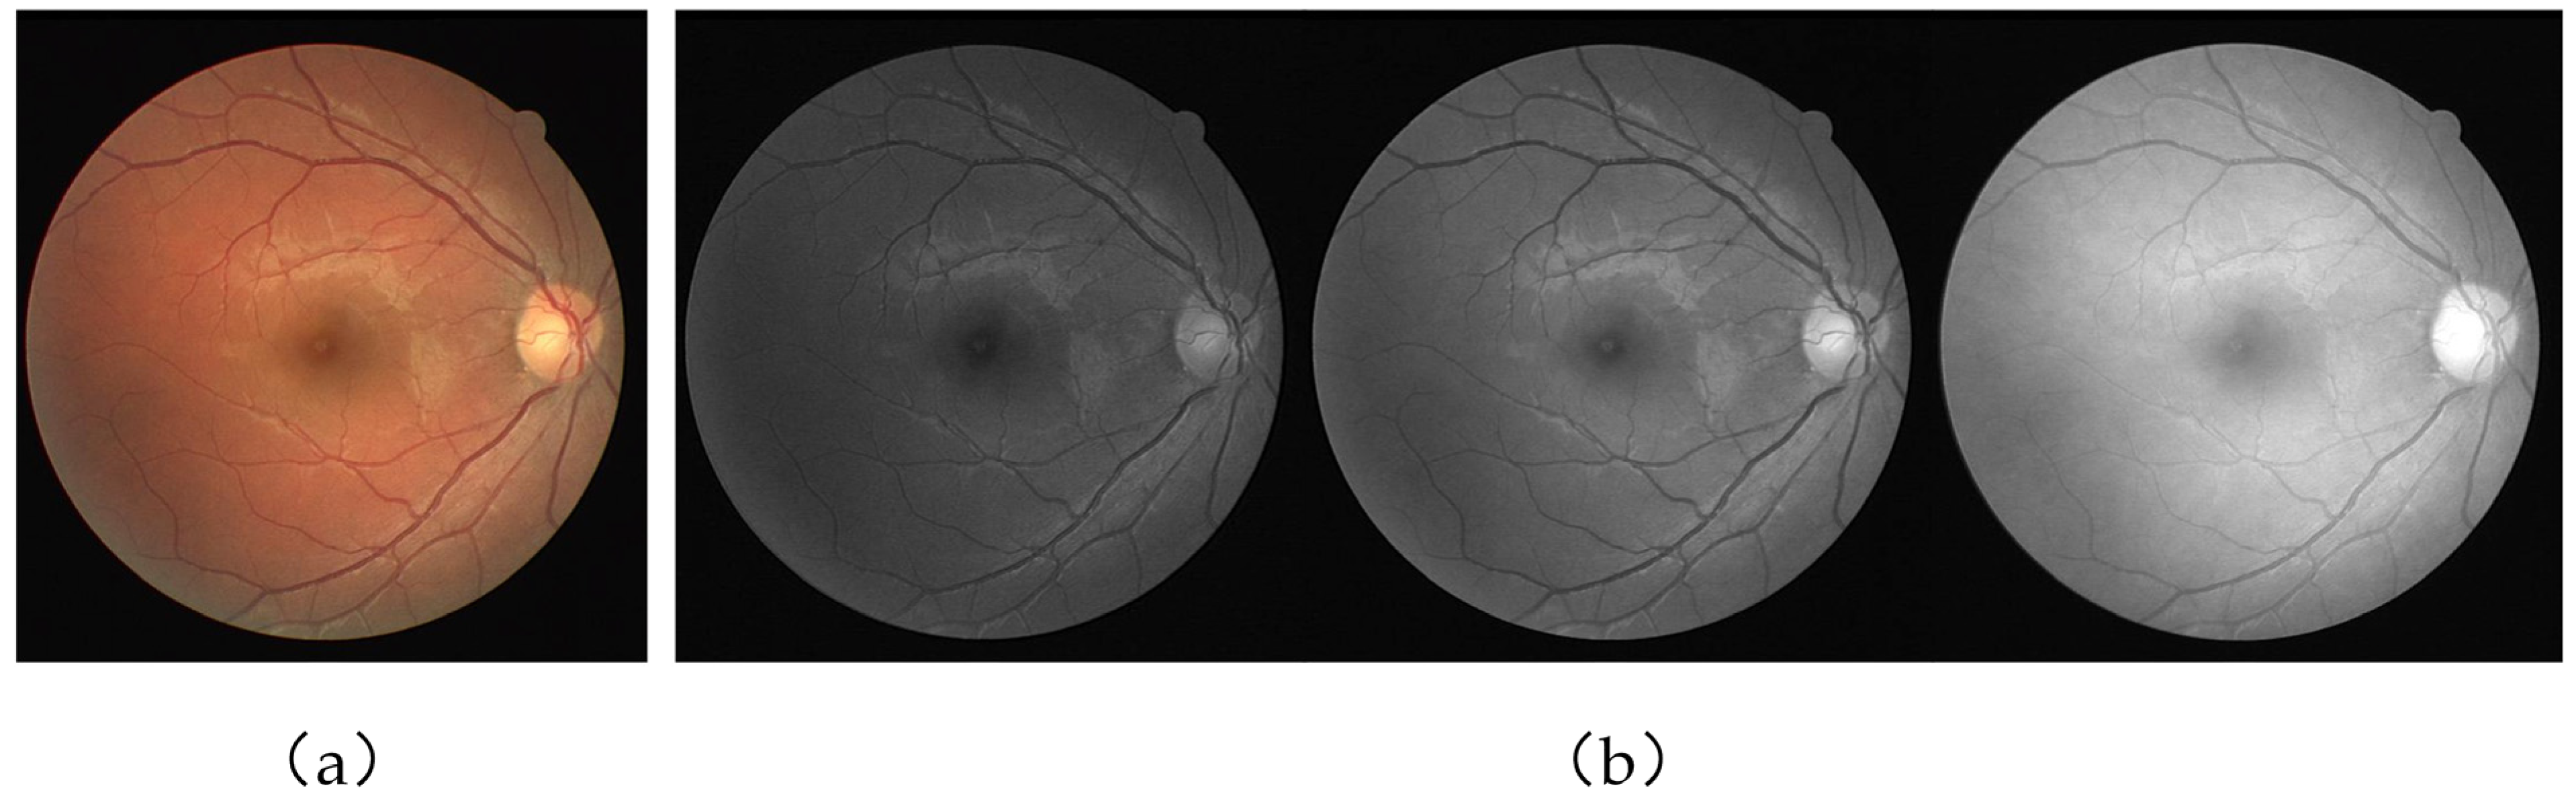

Figure 5 is a partial sample image of both datasets.

Figure 5. (a) DRIVE dataset and (b) CHASE_DB1 dataset. Looking from left to right, the leftmost column is the original image, the middle column is the corresponding ground truth, and the rightmost column is the corresponding mask.

Figure 6. Examples of image preprocessing. (a) Original image. (b) Image graying and image normalization.